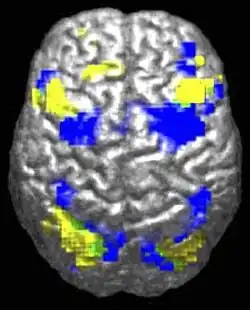

The beginnings of empathy lie in the brain. When a person empathises with another person, their brain triggers neurons that match the neurons in the brain of the person in distress. Or quite simply, just by perceiving an emotion in someone the neuron mechanisms that are responsible for that emotion in our brains are switched on. This phenomenon was first discovered from studies on rhesus monkeys, in which a class of neurons called mirror neurons were found in the ventral premotor and posterior parietal cortices in the brain. (Rizzolatti, Fogassi & Gallese, 2001 cited in Decety & Meyer, 2008). The evidence for mirror neurons in humans is a little less solid, however studies using functional magnetic resonance imaging (fMRI) have found similar results involving pain - when a person perceives someone in pain, the neural circuits for pain in the observer are activated, as if they too are experiencing pain (Decety & Meyer, 2008; Mikulincer & Shaver, 2010).

Empathy theorist Jean Decety also proposes that the experience of empathy likely involves other parts of the brain, such as the frontopariental and prefrontal circuits, as the person empathising must be able to differentiate himself or herself from the person in distress. In addition, executive functions instantiated in the prefrontal cortex may play a part, as this part of the brain helps to regulate emotions and yield mental flexibility (Decety & Meyer, 2008).

Empathy is visible in the brain, and likely involves ‘mirror neurons’ which help to replicate the emotion we perceive in our own brains. Empathy begins in children when they are born and gradually develops and matures throughout our lives.